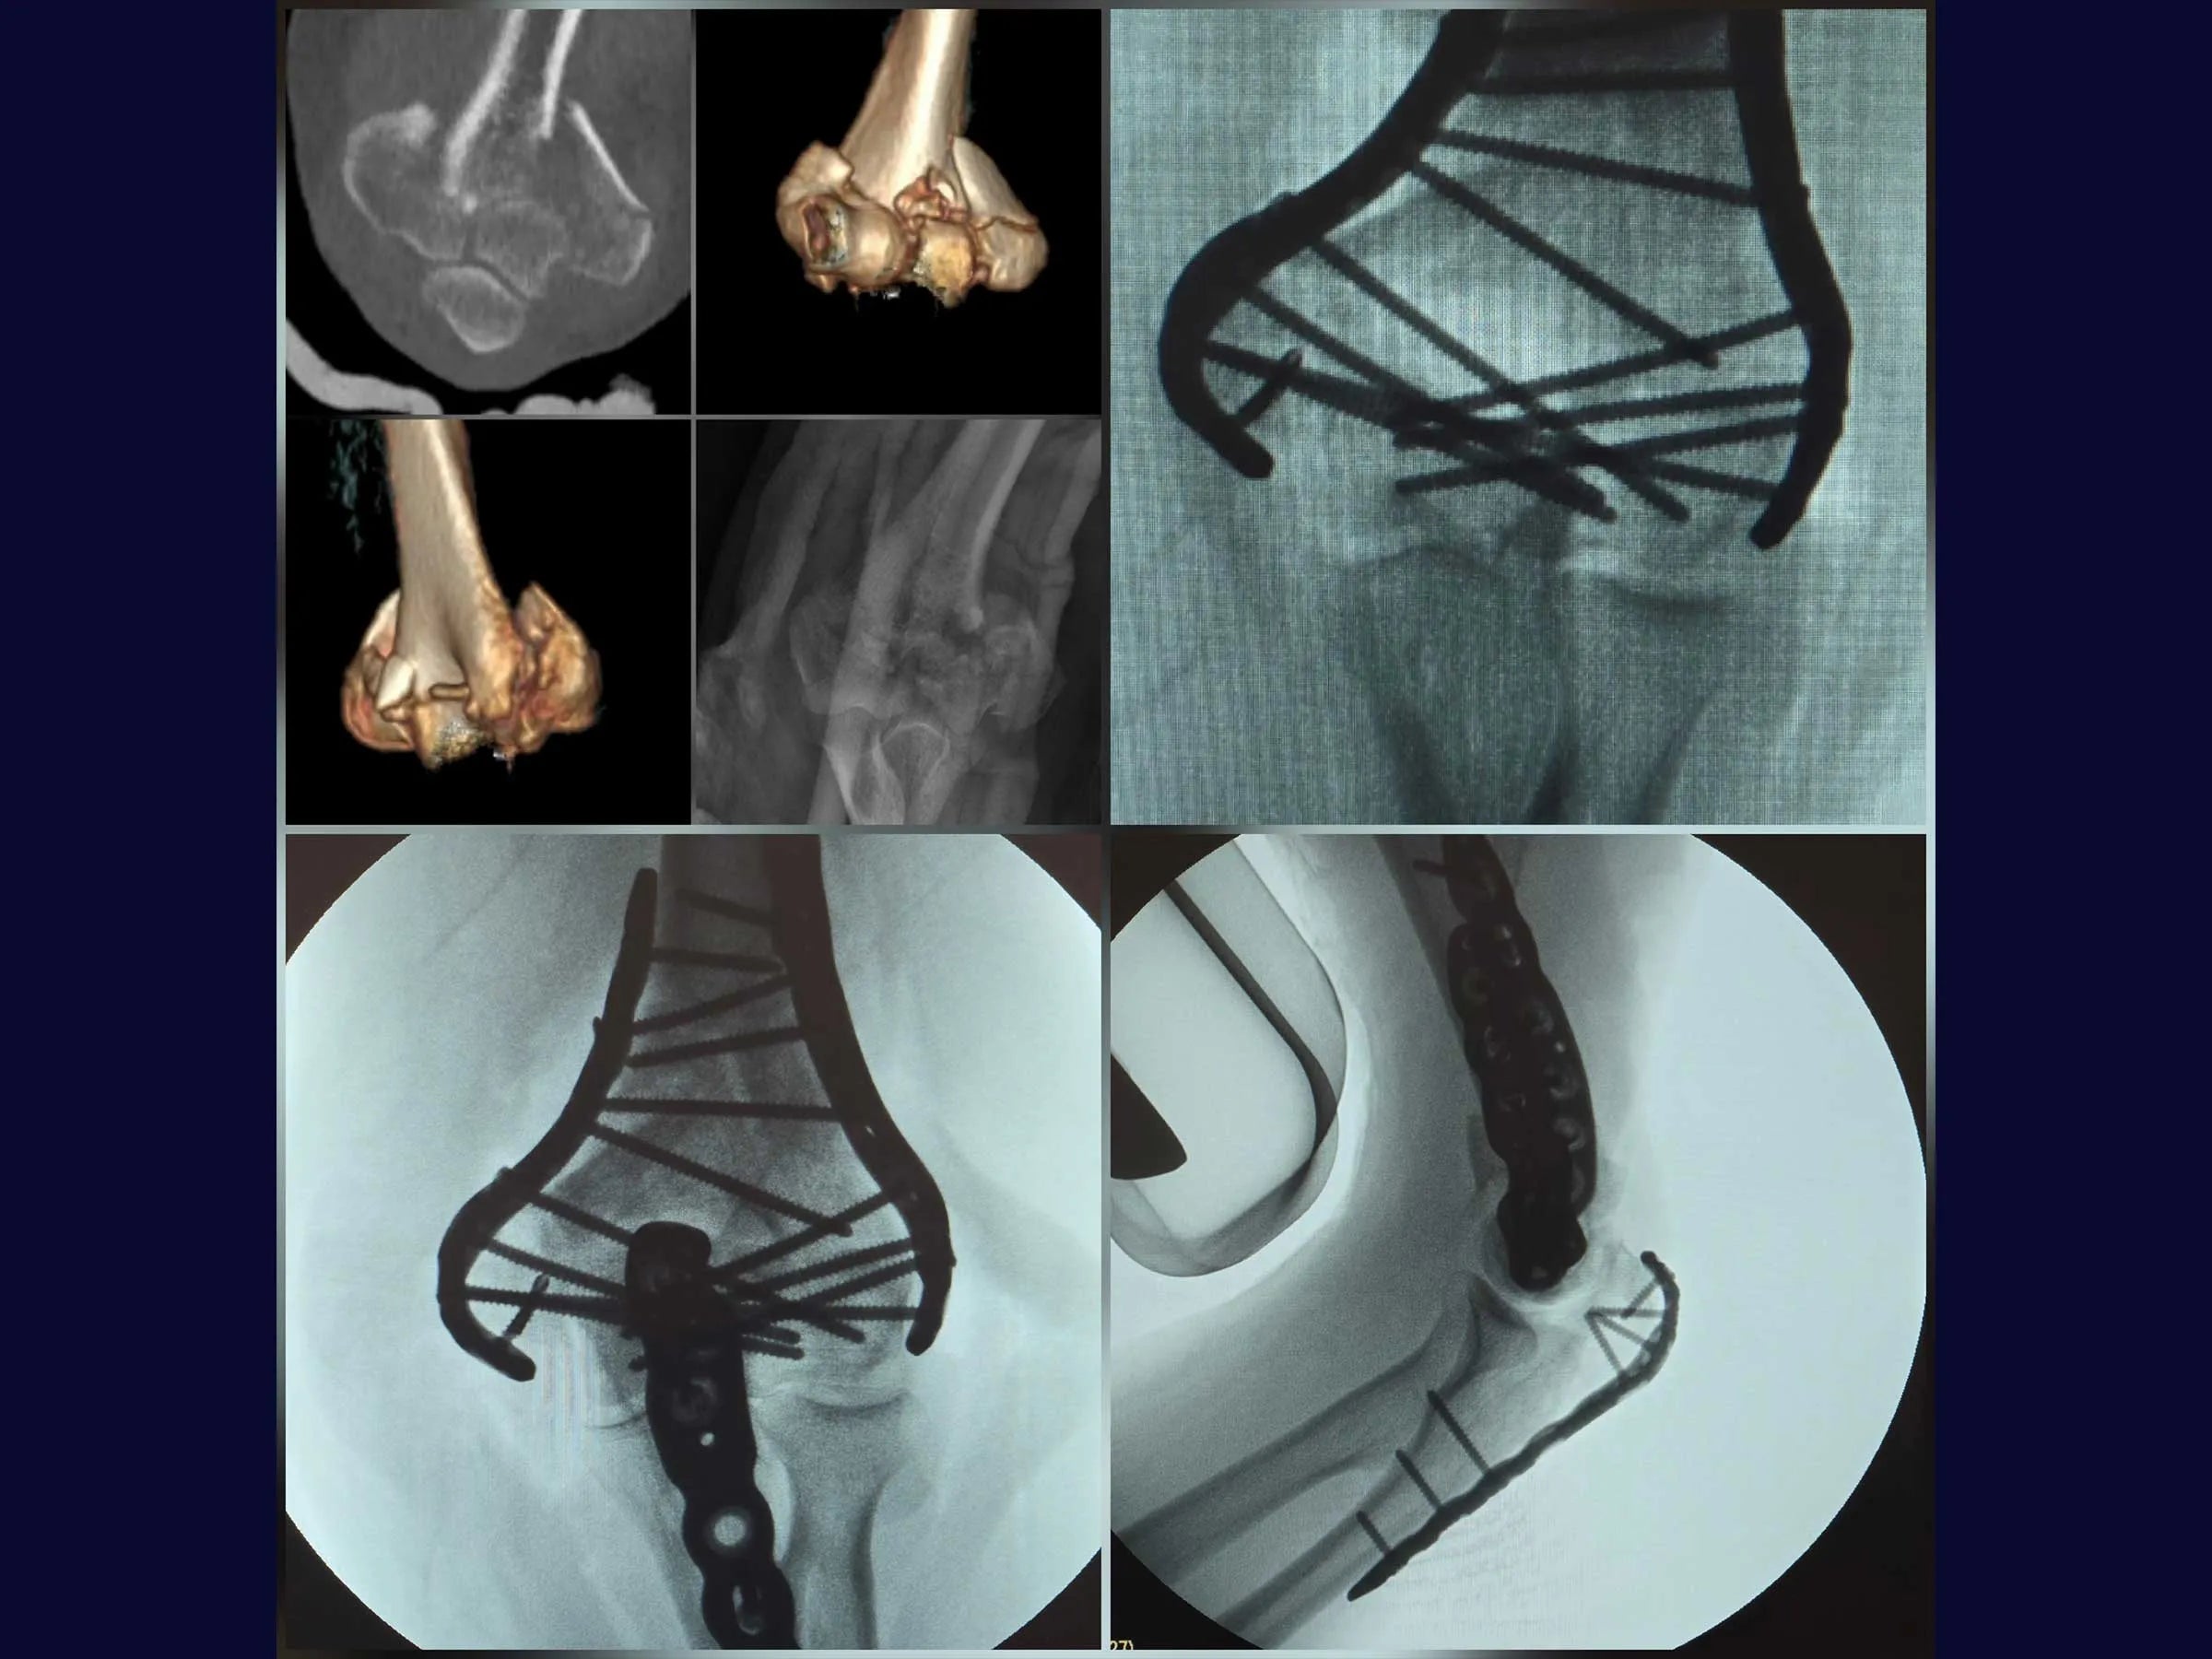

Fratura Articular Cominutiva do Úmero Distal

As fraturas articulares multifragmentares do úmero distal representam um dos maiores desafios na cirurgia do trauma, exigindo precisão na redução articular e estabilidade que permita mobilização precoce.

Este treinamento oferece uma visão detalhada da fixação rígida com placas de ângulo variável, apresentada em vídeo 4K sob a perspectiva cirúrgica, com comentários técnicos e material complementar em PDF.

- Osteotomia em Chevron no olécrano para ampla exposição articular.

- Redução de fragmentos articulares com fios de Kirschner em joystick.

- Fixação definitiva com placas bloqueadas de ângulo variável.

- Redução Controlada: Uso de fios K como joystick para manipulação de fragmentos articulares e restauração das colunas.

- Fixação Estável: Aplicação de placas bloqueadas de ângulo variável para alinhamento seguro e resistência biomecânica.